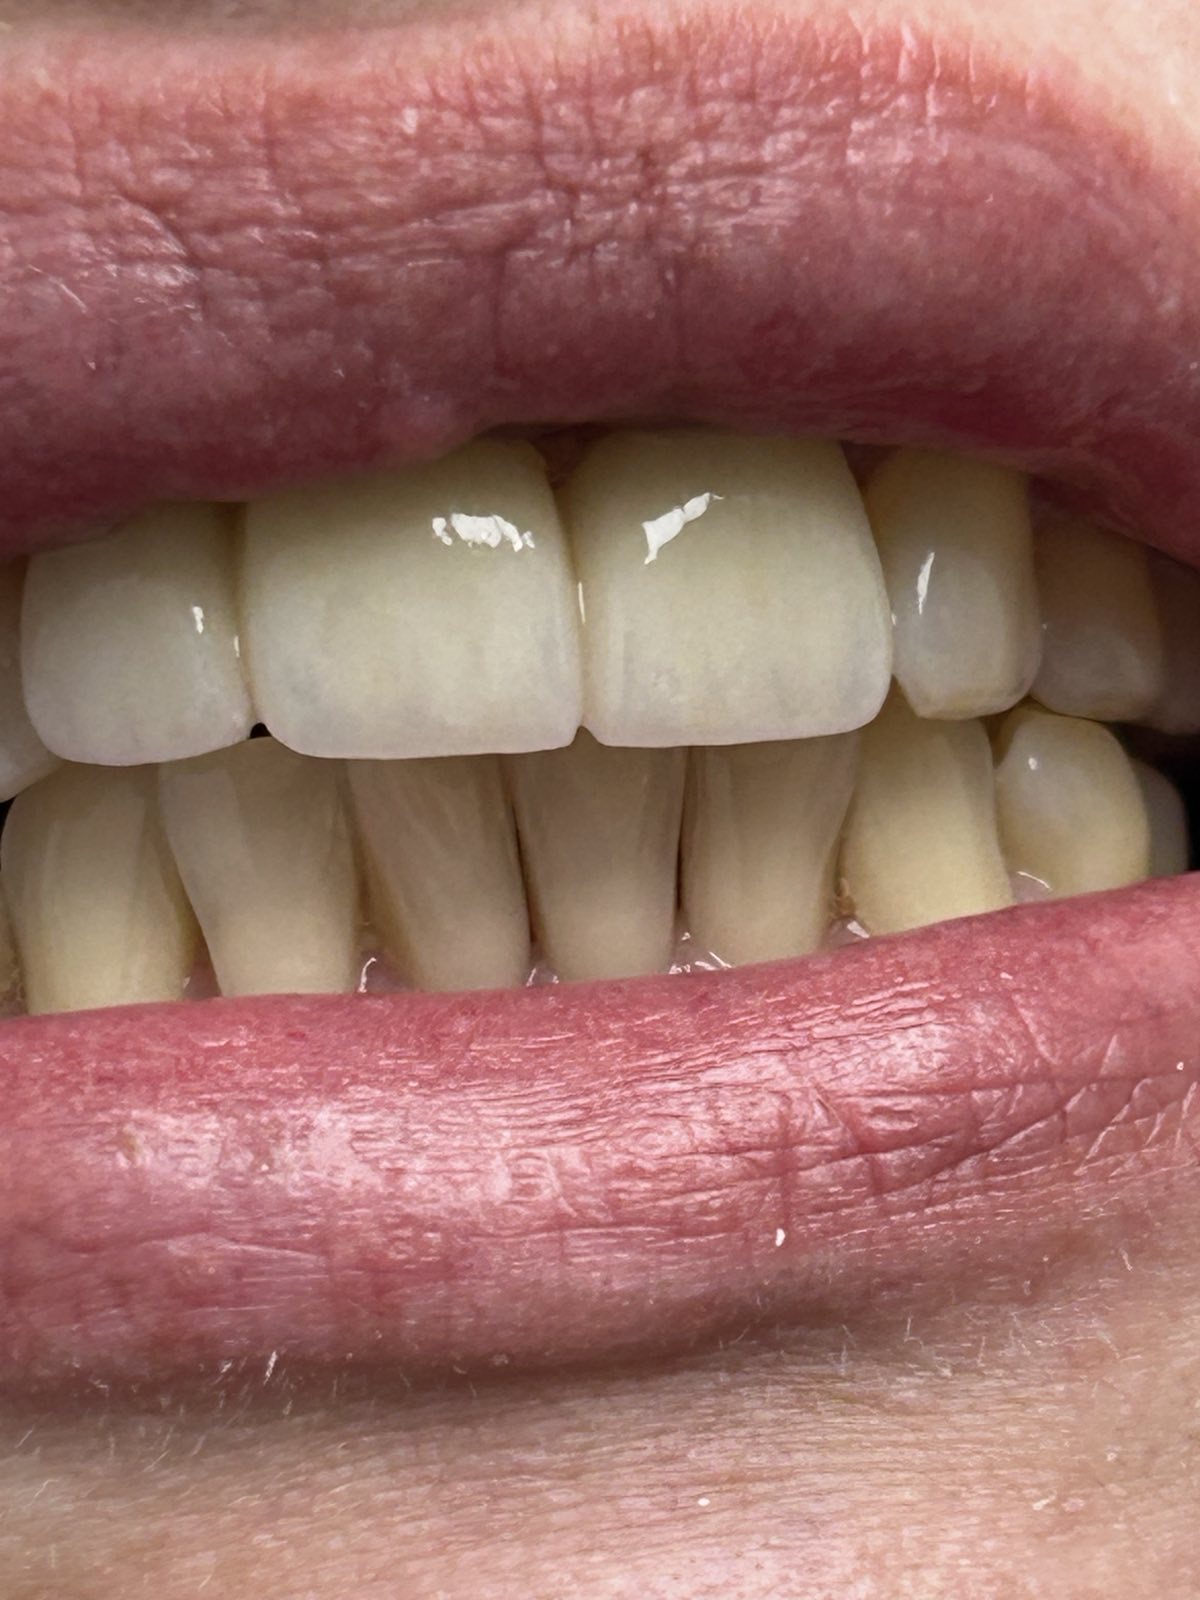

Пациентке предложено протезирование зубов коронками из диоксида циркония.

Работу выполнил стоматолог-ортопед Бернович Дмитрий Иосифович